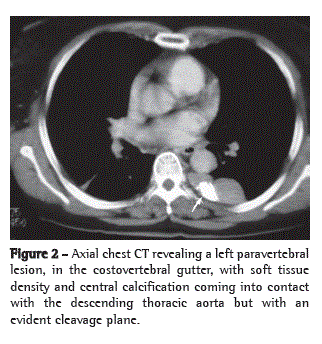

A chest X-ray revealed a mass in the region of the posterior mediastinum, which was confirmed by a preoperative chest CT scan, which identified a heterogeneous mass with dense calcification in the region of the left costovertebral gutter (Figures 1 and 2). The mass in the posterior mediastinum was resected together with the adjacent lung parenchyma. The histopathological examination revealed a lymph node whose architecture was partially distorted by spindle cell proliferation in close association with an inflammatory infiltrate, composed predominantly by lymphocytes. We identified characteristics that were definitely consistent with hyaline vascular-type Castleman's disease: follicles showing slight germinal center regression; a concentric arrangement of small lymphocytes; and collagenous stroma. The proliferating spindle cells formed spiral fascicles and matrices, with cells with ill-defined borders, vesicular nuclei, and distinct nucleoli, with little variation in nucleus size, as well as varying degrees of atypia, morphologically consistent with follicular dendritic cell sarcoma. Immunohistochemical analysis was negative for the following markers: 40-, 48-, 50-, and 50.6-kDa cytokeratins; CD30; CD246; CD21; CD23; CD4RB; CD68; smooth muscle actin; and